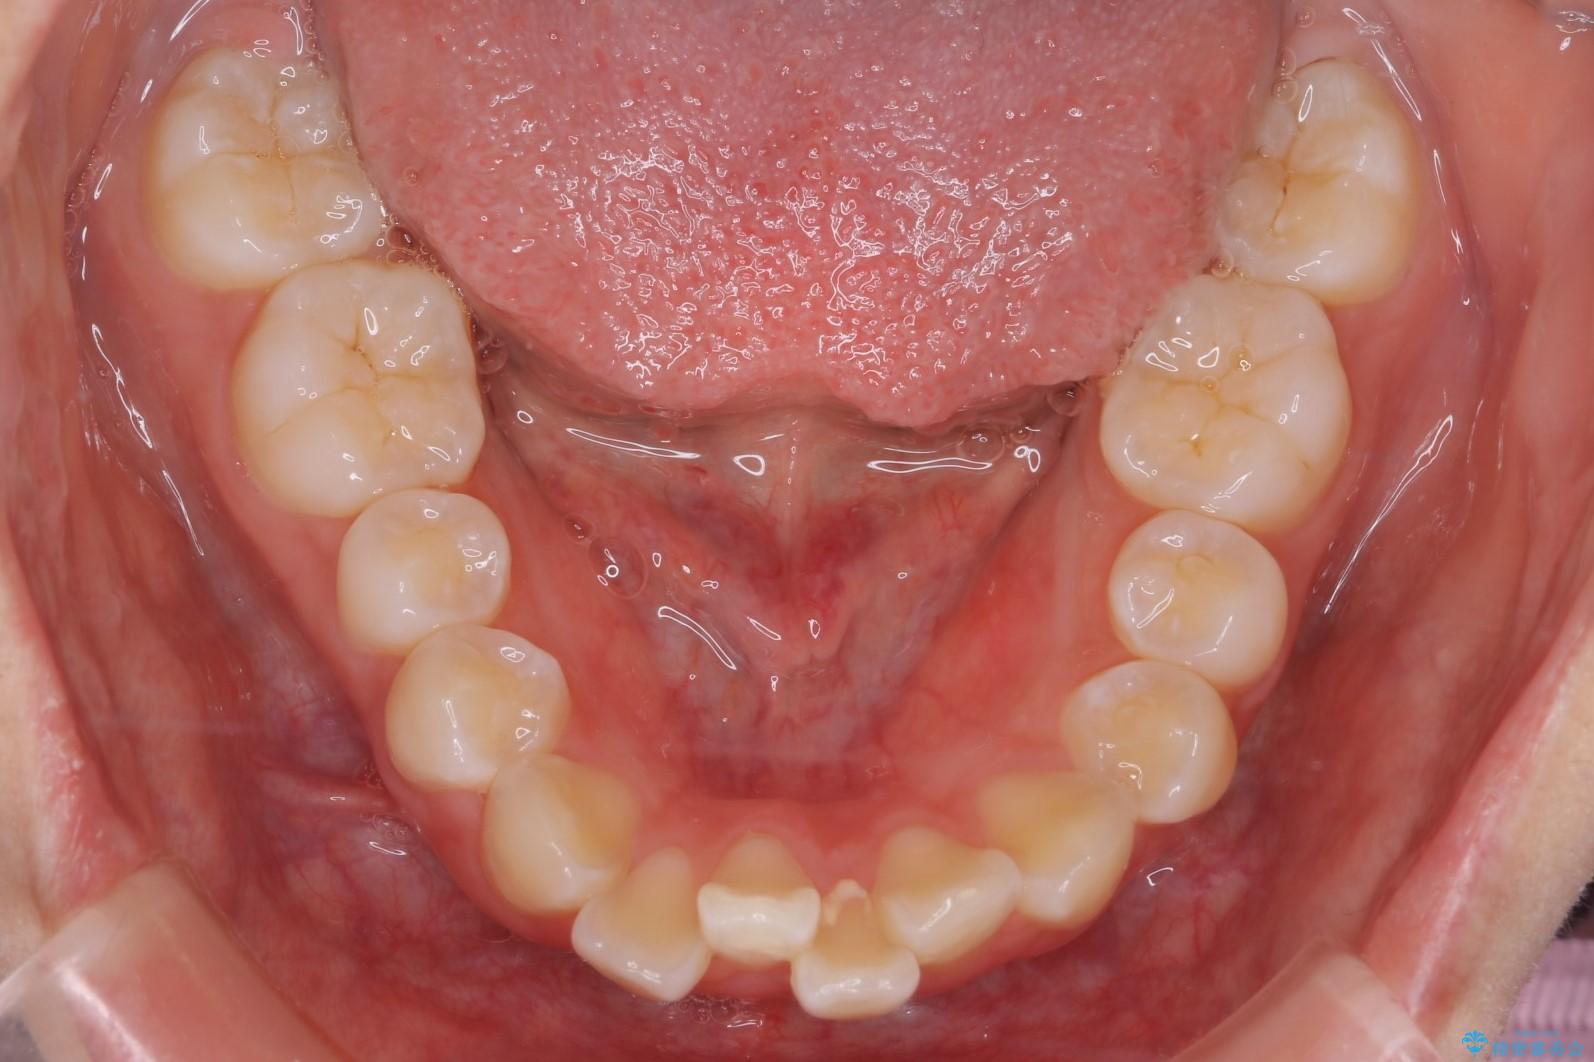

前歯のガつきと口元が出ていることを気にされご来院された患者様です。

上下4番目の歯を抜歯してガタつきを改善しながら口元を下げる治療計画を立てました。